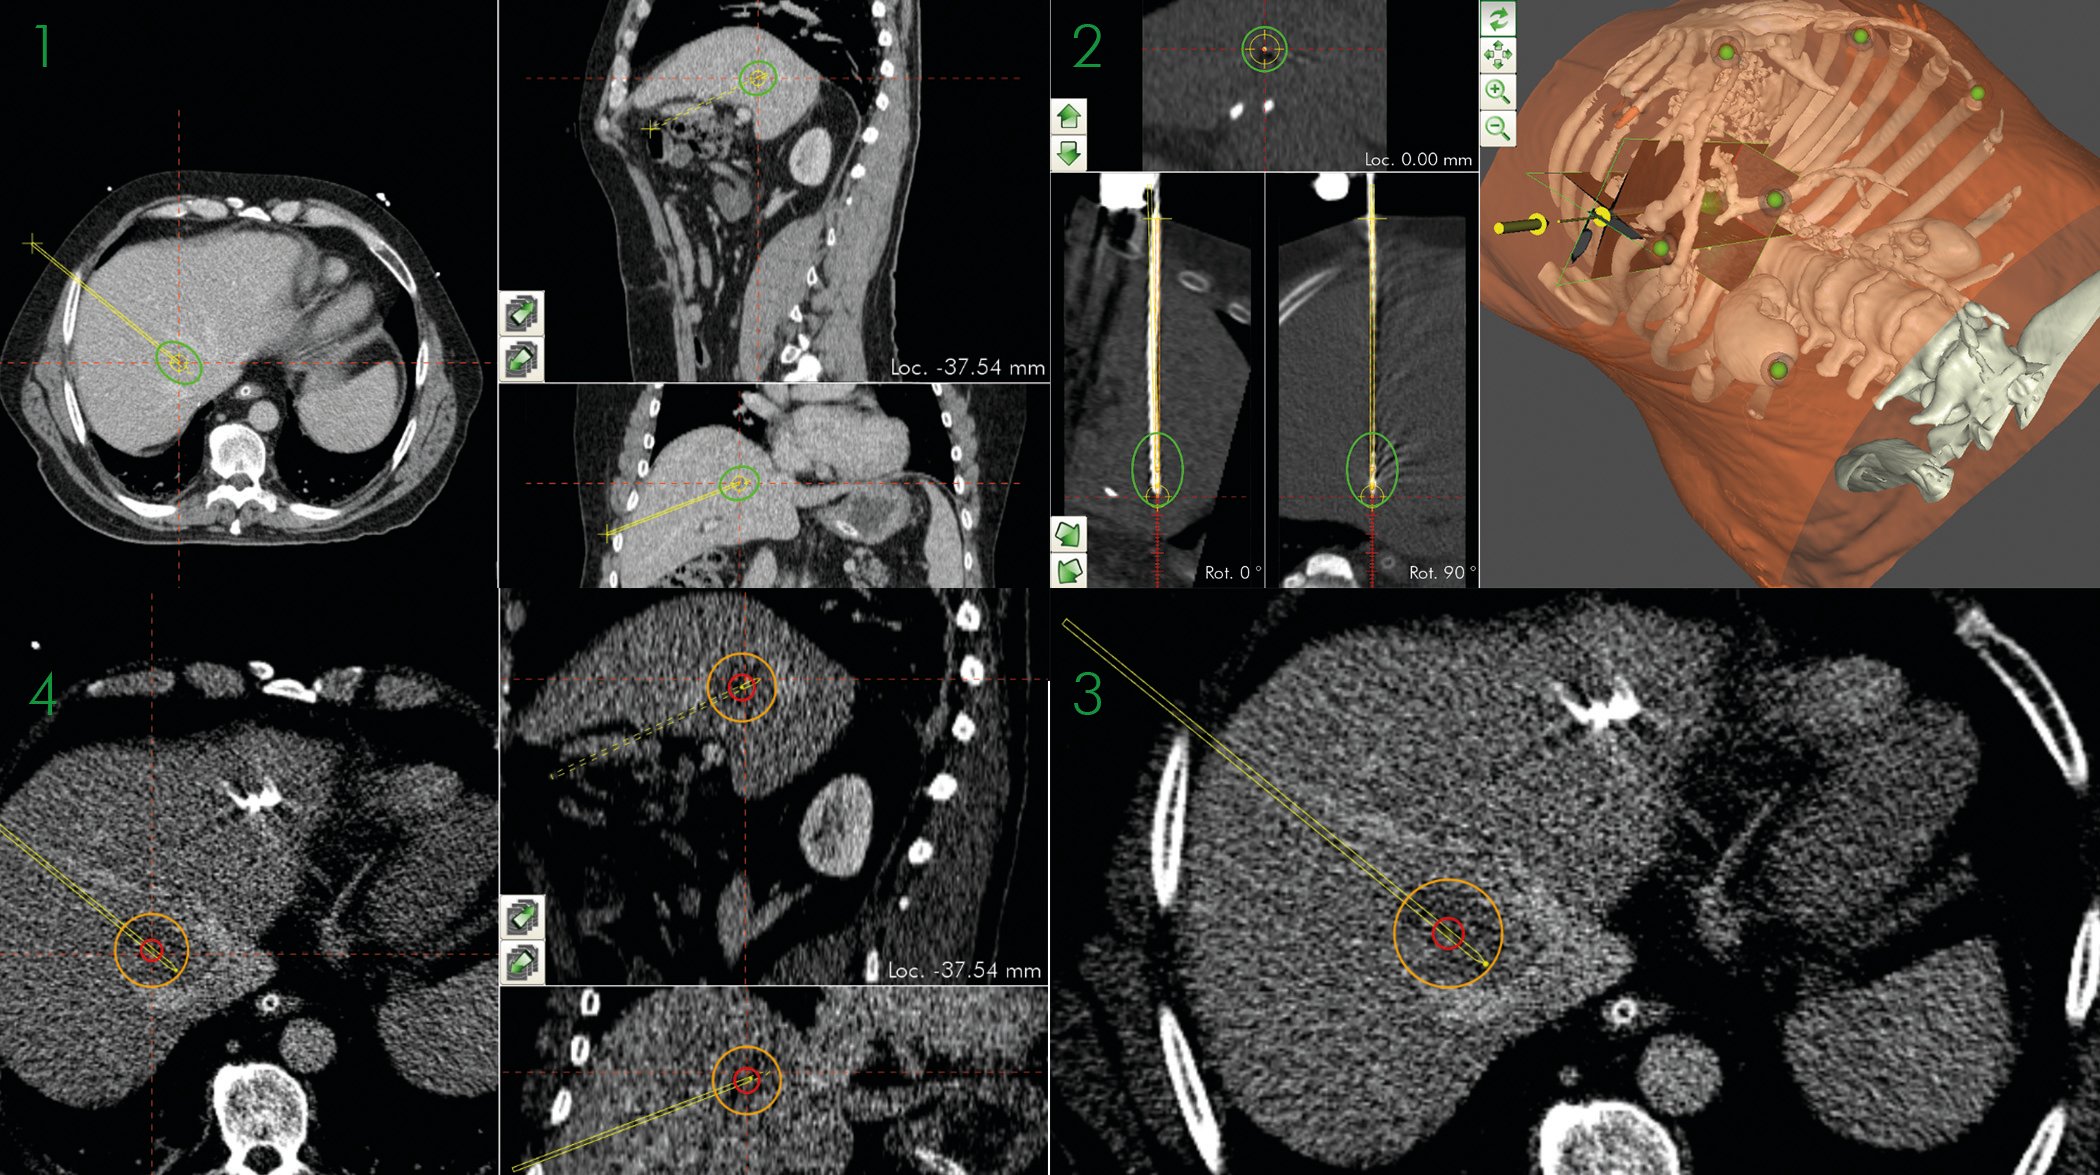

From www.cascination.com

CTguided ablation of a deep seated hepatic tumor in segment VIII Liver Biopsy And Ablation What is secondary liver cancer? Secondary cancer in the liver happens when cancer cells spread to the liver from a primary cancer somewhere else in the body. These techniques can be used in patients with a few small tumors and. Chemotherapy for secondary liver cancer. Understand the main types of treatment for liver cancer, including surgery, chemotherapy, radiotherapy, ablation therapy. Liver Biopsy And Ablation.